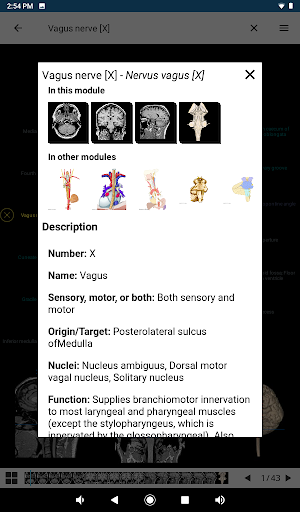

- Toque las etiquetas para mostrar las estructuras anatómicas

*Vista detallada mejorada de partes anatómicas para una identificación más fácil en imágenes del módulo actual y otros.

*Visibilidad mejorada de las definiciones de partes anatómicas

la vista de detalles de una estructura anatómica ahora se muestran los términos relacionados